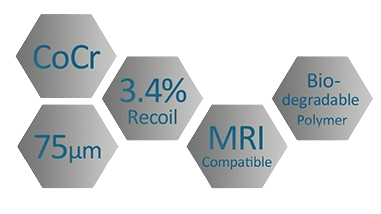

Gureater ™ CoCr Stent with Sirolimus Coating

GuReater™ is a Cobalt-Chrome drug-eluting stent coated with Sirolimus.

Its 75 μm CoCr struts provide excellent flexibility and crossability, ensuring optimal vessel conformity after implantation.

Available in a wide range of sizes, the Gureater drug-eluting stent features a cobalt-chrome (CoCr) platform with a bioabsorbable polymer (PLGA) that promotes early endothelialisation, helping to prevent inflammation.

Combined with Sirolimus, it offers excellent drug-release control over a total period of 90 days. Its design ensures high flexibility, optimal crossability, and low recoil.

Features

The Co-Cr stent offers high radiopacity and biocompatibility, providing an excellent balance between radial strength and flexibility.

%

MRI Compatible

%

Low Recoil Ratio

%

Excelent Compliance

µm

Strut Thickness